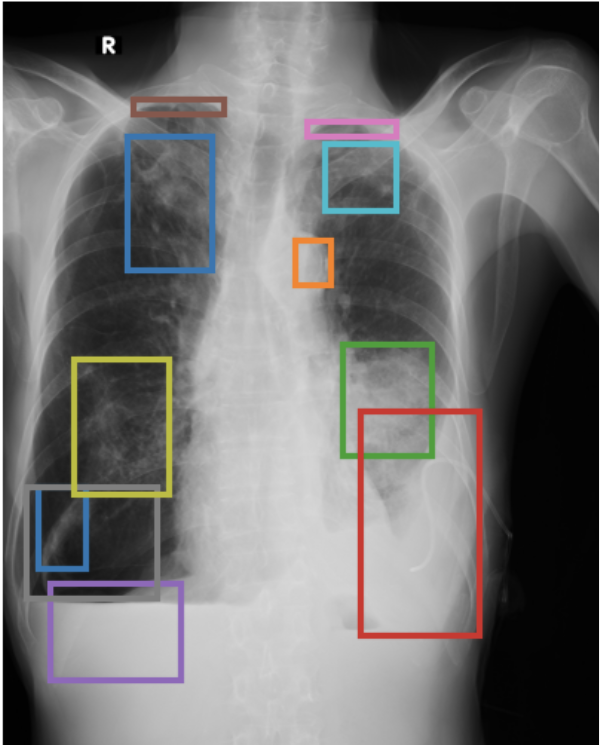

To address these drawbacks, state-of-the-art models such as MAIRA-2 [3] explicitly incorporate grounded report generation to better align local visual evidence with the textual findings. For example, MAIRA-2 is trained on a diverse set of localization-based tasks, including phrase grounding and grounded report generation. However, as shown in Figure 1, current models often exhibit a bias in which the target visual regions become overly associated with abnormal findings, leading to false positives in medical reports.

As shown in Table 1, our data composition reflects this imbalance: over 12.9M instances from Chest ImaGenome dominate the much smaller MS-CXR (815 PG instances) and PadChest-GR (12k instances) datasets. Beyond the imbalance between datasets, each dataset also exhibits substantial intra-dataset class imbalance. For example, anatomical regions in AGRG and semantic categories in PG are unevenly represented, leading the model to overfit frequent regions, neglect rare but clinically important ones, and hallucinate findings (Figure 1). Our curriculum framework addresses both sources of imbalance.